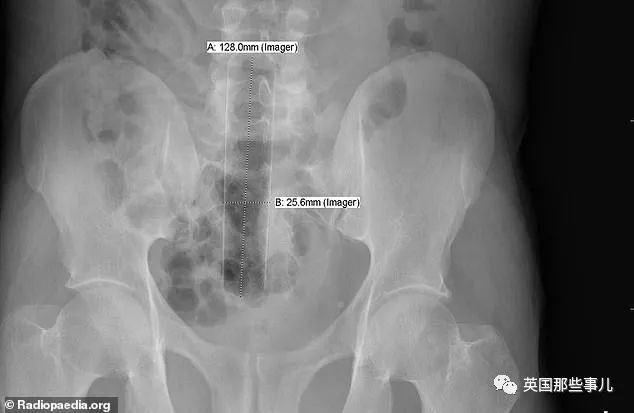

“噴霧罐子”

“長約13cm的金屬雪茄管”